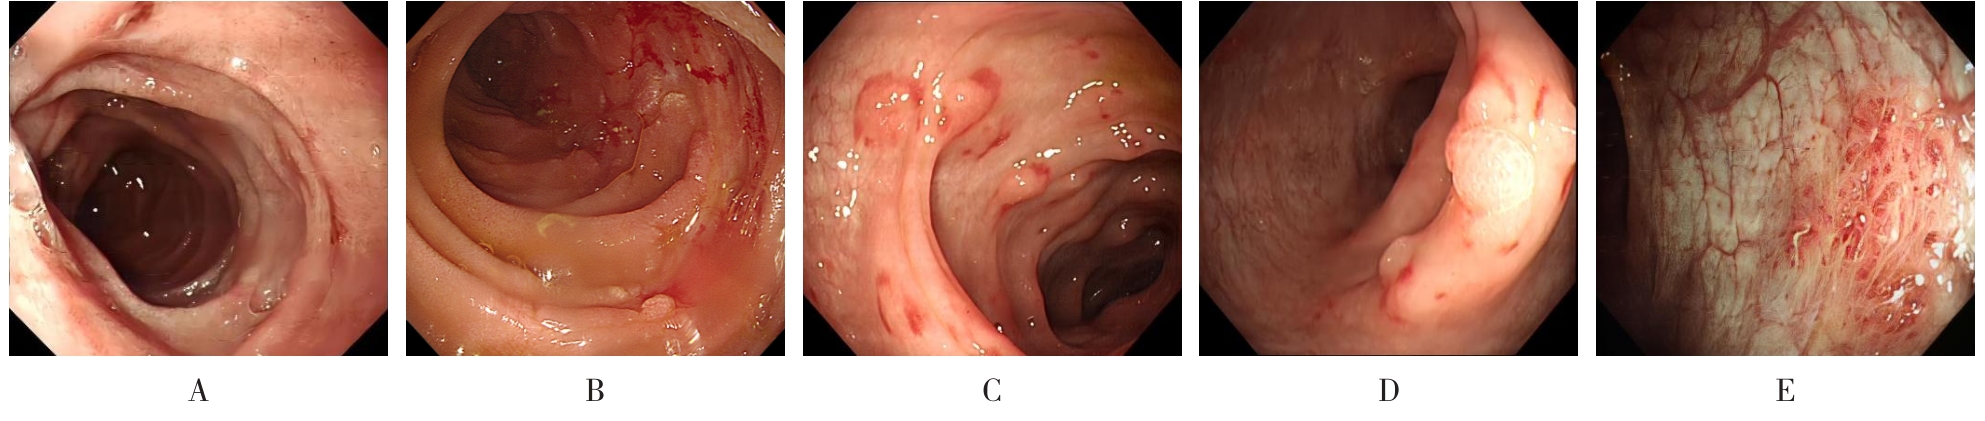

• 获得性免疫缺陷综合征合并马尔尼菲篮状菌导致肠道感染的内镜下表现(附6例报告)

2026, 32(3):84-88. DOI: 10.12235/E20250461

摘要 (32) HTML (27) PDF 3.50 M (26) 评论 (0) 收藏

摘要:目的 探讨获得性免疫缺陷综合征(AIDS)合并马尔尼菲篮状菌(TM)感染导致肠道感染的内镜下特征。方法 回顾性分析2022年11月-2024年10月于该院确诊为AIDS合并TM感染导致肠道感染的6例患者的临床资料。包括:临床症状、实验室检查、影像学检查、内镜检查和病理检查等。结果 6例患者中,男5例,女1例;发病年龄26~67岁;AIDS合并TM感染导致肠道感染患者的临床表现为:腹泻、腹痛、腹胀和恶心呕吐。其中,2例有消化道出血表现。实验室检查:6例患者外周血白细胞计数为(1.37~4.49)×109/L,血红蛋白计数为(67~99)g/L;CD4+T淋巴细胞为(1~52)个/μL,CD8+ T淋巴细胞为(61~321)个/μL,CD4+T淋巴细胞/CD8+T淋巴细胞比值为(0.01~0.18)。6例患者均行HIV RNA检测。其中,5例HIV RNA阳性。血培养:可见丝状真菌,报告显示为TM。影像学检查:6例患者CT结果可见肠系膜及腹膜后多发淋巴结肿大。内镜检查:6例患者内镜下均可见肠道病变。其中,十二指肠糜烂溃疡2例,结肠多发糜烂溃疡4例。病理检查:6例患者幽门螺杆菌(Hp)结果均为阴性,黏膜下可见成簇的小球形真菌孢子,符合TM感染;特殊染色:PAS(+),六胺银染色(+)。结论 当AIDS晚期患者出现消化道症状时,应警惕TM感染,病变部位常见于全结肠和直肠,亦可累及十二指肠,内镜下表现多为溃疡、糜烂和隆起性病变,形态表现无特异性;及时行胃肠镜检查、病理活检、特殊染色和免疫组化是确诊的关键。